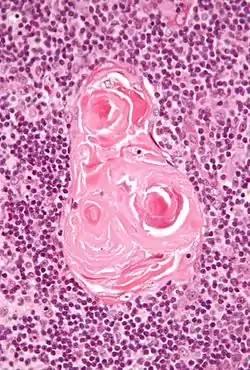

Micrograph of a thymic corpuscle. H&E stain.

Hassall's corpuscles (or thymic corpuscles (bodies)) are structures found in the medulla of the human thymus, formed from eosinophilic type VI epithelial reticular cells arranged concentrically. These concentric corpuscles are composed of a central mass, consisting of one or more granular cells, and of a capsule formed of epithelioid cells. They vary in size with diameters from 20 to more than 100μm, and tend to grow larger with age.[1] They can be spherical or ovoid and their epithelial cells contain keratohyalin and bundles of cytoplasmic fibres.[2] Later studies indicate that Hassall's corpuscles differentiate from medullary thymic epithelial cells after they lose autoimmune regulator (AIRE) expression.[3] This makes them an example of Thymic mimetic cells.[4] They are named for Arthur Hill Hassall, who discovered them in 1846.[5][6]